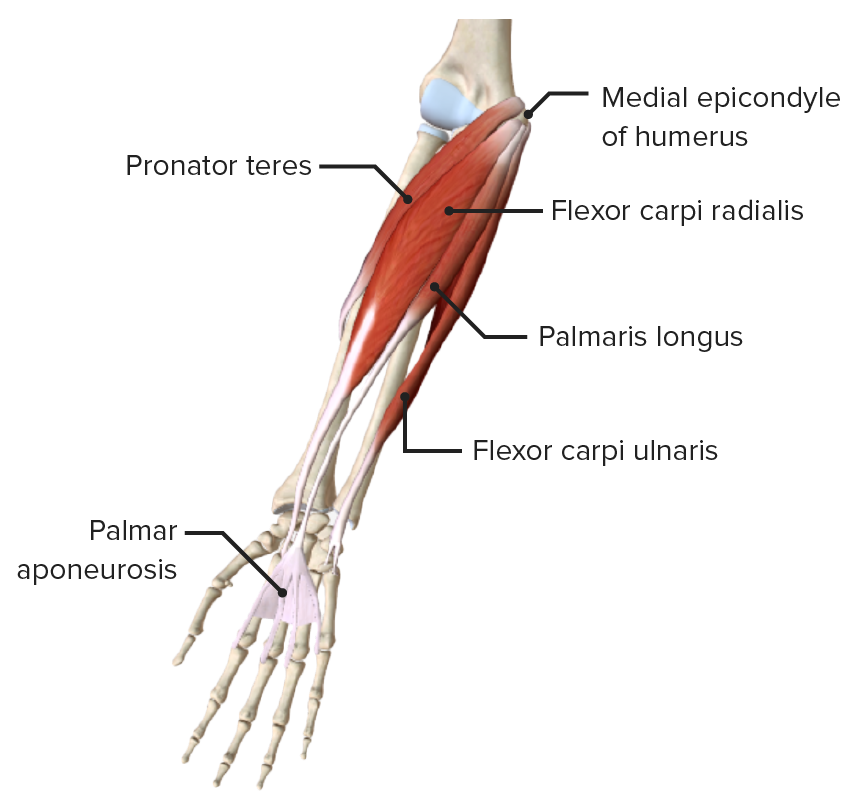

Forearm Anatomy Concise Medical Knowledge

Placements of FSRs on forearm muscles. A Ventral view of right online, Muscles of the Anterior Forearm Superficial View Learn Muscles online, Forearm Anatomy Concise Medical Knowledge online, Right Forearm Anatomy by joechez on DeviantArt online, Forearm Anatomy Concise Medical Knowledge online, Anterior Forearm Basicmedical Key online, Human Anatomy for the Artist The Dorsal Forearm Part 1 online, Anterior Forearm Basicmedical Key online, Right Anterior Forearm Muscles Diagram Quizlet online, Lateral cutaneous nerve of forearm Wikipedia online, Muscles of the Anterior Forearm Deep View Learn Muscles online, Forearm Anatomy Concise Medical Knowledge online, Solved Fig. 13.8 a Pight forearm anterior view b Right online, 7. Muscles of the Forearm and Hand Musculoskeletal Key online, Placements of FSRs on forearm muscles. A Ventral view of right online, Anatomy of the Forearm Trial Exhibits Inc online, Forearm Anatomy Concise Medical Knowledge online, superficial muscles of right forearm Diagram Quizlet online, U.Br.Columbia Drawing Extensor aspect of right forearm English online, Individual Muscles of Forearm Rotators of Radius Anatomy Right online, Dr Shahbaz Ashraf PT Right Anterior Forearm Superficial Muscles online, My study of the right forearm r learnart online, Right and Left Sided Forearm Pain Causes Treatments Buoy online, Right Anterior Forearm Superficial View Diagram Quizlet online, Skin Forearm Right Complete Anatomy online, Forearm Muscle Strain online, 1 Complete view of the forearm. Right forearm. Anterior view online, Persistent Right Forearm Nonunion and Angulation online, X ray Right Forearm AP LAT View Test Price in Delhi Ganesh online, Forearm Anatomy Concise Medical Knowledge online, Forearm pain Causes exercises and stretches online, bones of the right forearm Quiz online, Right Forearm Bones Radius Ulna Anterior View Black White online, U.Br.Columbia Drawing Superficial and deep dissection of right online, Illustration of dissection of the right forearm and elbow online.

Placements of FSRs on forearm muscles. A Ventral view of right online, Muscles of the Anterior Forearm Superficial View Learn Muscles online, Forearm Anatomy Concise Medical Knowledge online, Right Forearm Anatomy by joechez on DeviantArt online, Forearm Anatomy Concise Medical Knowledge online, Anterior Forearm Basicmedical Key online, Human Anatomy for the Artist The Dorsal Forearm Part 1 online, Anterior Forearm Basicmedical Key online, Right Anterior Forearm Muscles Diagram Quizlet online, Lateral cutaneous nerve of forearm Wikipedia online, Muscles of the Anterior Forearm Deep View Learn Muscles online, Forearm Anatomy Concise Medical Knowledge online, Solved Fig. 13.8 a Pight forearm anterior view b Right online, 7. Muscles of the Forearm and Hand Musculoskeletal Key online, Placements of FSRs on forearm muscles. A Ventral view of right online, Anatomy of the Forearm Trial Exhibits Inc online, Forearm Anatomy Concise Medical Knowledge online, superficial muscles of right forearm Diagram Quizlet online, U.Br.Columbia Drawing Extensor aspect of right forearm English online, Individual Muscles of Forearm Rotators of Radius Anatomy Right online, Dr Shahbaz Ashraf PT Right Anterior Forearm Superficial Muscles online, My study of the right forearm r learnart online, Right and Left Sided Forearm Pain Causes Treatments Buoy online, Right Anterior Forearm Superficial View Diagram Quizlet online, Skin Forearm Right Complete Anatomy online, Forearm Muscle Strain online, 1 Complete view of the forearm. Right forearm. Anterior view online, Persistent Right Forearm Nonunion and Angulation online, X ray Right Forearm AP LAT View Test Price in Delhi Ganesh online, Forearm Anatomy Concise Medical Knowledge online, Forearm pain Causes exercises and stretches online, bones of the right forearm Quiz online, Right Forearm Bones Radius Ulna Anterior View Black White online, U.Br.Columbia Drawing Superficial and deep dissection of right online, Illustration of dissection of the right forearm and elbow online.